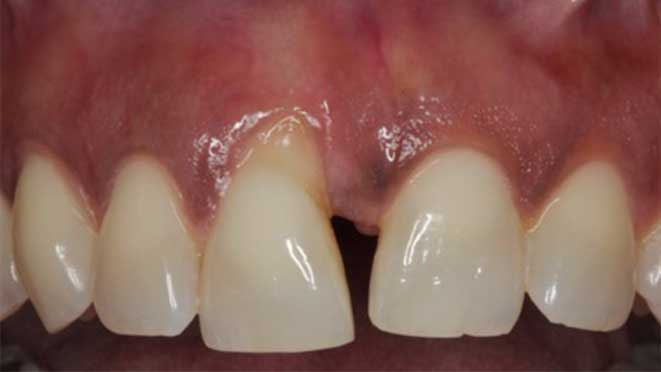

All on 4 dental implants are a type of dental restoration that provides a permanent alternative to traditional dentures and bridges. Unlike other options, All on 4 implants require only four arches of dental implants, which can be implanted at an angle in cases of minimal bone height. This innovative technique provides maximum support and allows for a complete set of teeth with minimal implants.

The process of implantation involves an initial consultation with a dental professional, followed by surgery for the implantation of temporary prosthetics. Following this, a healing period is required before the design of the permanent prosthetic set can be completed. This process typically takes a few months to complete.